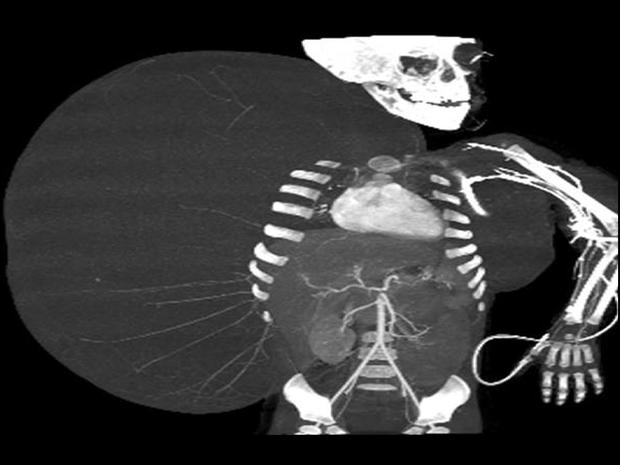

33-pound tumor

In this still image taken from an undated video released by the Mexican Social Security Institute (IMSS) on Tuesday, June 26, 2012, an image created through medical imaging technology shows an X-ray-like image of 2-year-old Jesus Rodriguez, prior to having a benign tumor removed from his body. Mexican doctors successfully removed a 33 pound tumor from the toddler that was heavier than his body weight.